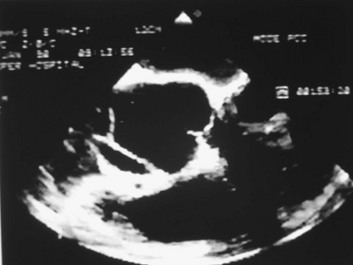

Transthoracic echocardiography (TEE) (Fig. 33.5) can be performed safely on most critically ill patients in a monitored setting.19,20 To avoid precipitating hypertension, tachycardia, or gagging (straining) in a patient with suspected dissection, conscious sedation should be administered. Nearly all of the thoracic aorta can be visualized, including most of the arch. The area from the distal ascending aorta to the midarch, however, is difficult to evaluate with TEE because of interposition of the airway between the esophagus and the aorta.21 The sensitivity of TEE for thoracic aortic dissection is close to 100%, but specificity is lower, owing primarily to reverberation artifacts that may be visualized within the ascending aorta, simulating an intimal flap.22 Color flow Doppler with TEE may demonstrate flow through or on either side of the suspected intimal flap (Fig. 33.6). TEE is helpful for evaluating involvement of the coronary ostia and aortic valve. As with TTE, regional and overall ventricular wall motion can be evaluated and the presence of pericardial effusion can be determined.